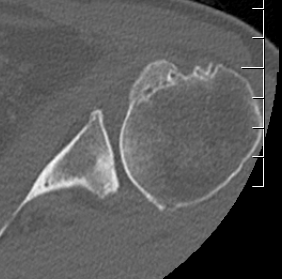

Type A2 Type B1

Type B2 Type B3

Type B3